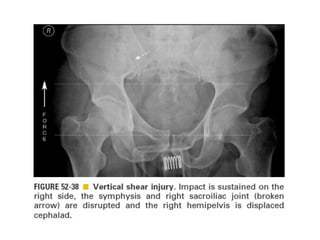

Skeletal trauma was presented by Dr Laith Fadhel with reference to Grainger's Diagnostic Radiology textbook. The presentation covered skeletal trauma as assessed through diagnostic radiology techniques. Key findings and treatments for skeletal injuries were likely discussed.